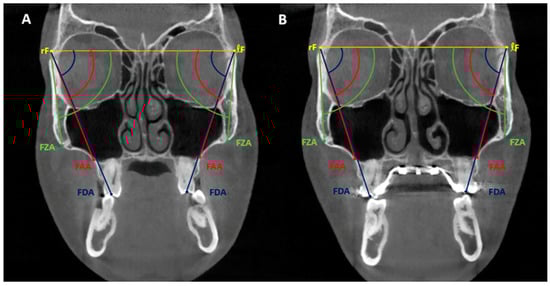

The transverse deficiency was diagnosed using coronal cuts from each subject’s initial CBCT according to Paredes et al. [32]. The maxillary bone width was determined by the distance between the right and left bony points at the level of the mesiobuccal root tips of the upper first molars (usually the narrowest part of the maxilla). Mandibular bone width was defined as the distance between the right and left bony buccal surfaces at the level of the lower first molar furcation. If the mandibular width was greater than the maxillary width, a transverse discrepancy was diagnosed. Clinically and in dental casts, the maxillary width is defined by the distance between the left and right most concave points along the maxillary vestibule above the mesiobuccal cusps of the first molars [34]. The mandibular width is defined as the distance between the left and right buccal surfaces over the lower first molar furcation. The amount of difference among these values also projects the extent of maxillary skeletal expansion required (Figure 1).

Figure 1.

Method used clinically and in dental casts to project the extent of maxillary skeletal expansion required. Blue line (the distance between the narrowest points of the maxillary sulcus area above the mesiobuccal cusps of the first molars), maxillary width, and red line (the distance between the projected points on the mandibular buccal surfaces at the level of furcation), mandibular width, measured with a digital caliper.